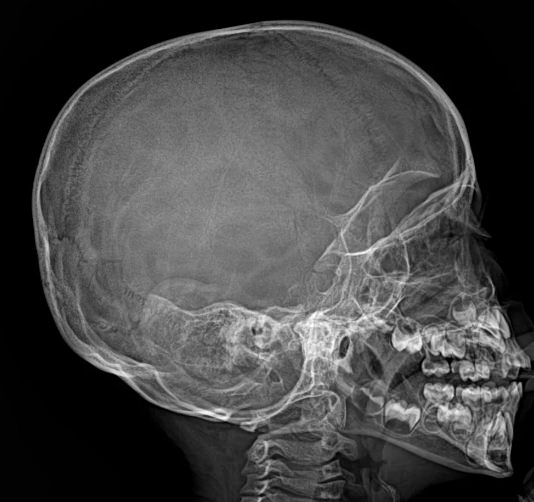

Диагностика выполняется без подготовки. Пациент снимает с головы и шеи украшения, очки, съемные протезы и надевает защитный фартук. Далее надо встать или сесть возле пластины детектора и прижаться к ней лбом и носом или щекой. Рентгенолаборант показывает, как правильно держать голову для нужной проекции.

Во время снимка нельзя двигаться, сглатывать слюну и дышать. Но обычно это несложно, так как снимок длится буквально 1 секунду. Его описание рентгенолог сделает в этот же день